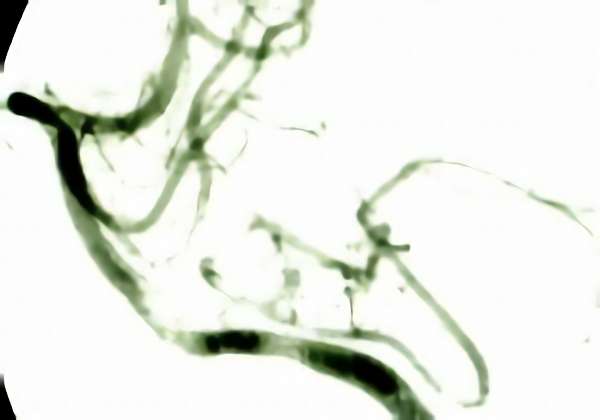

'19年5月

右中小脳脚 出血再発

SM 3(S1,E1,V1)

米国の病院

No.359 モニタリング

No.359 手術前

No.359 手術中

No.359 手術後

出血既往があり。2回の手術前血管内手術の後に、

Lateral transpeduncular approachにより再々出血予防を目的に

摘出手術を行う。完全摘出であることを確認した。

手術による合併症や後遺症なしで退院した。経過良好。